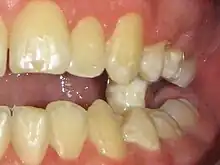

- Béance - Il existe un espace vertical libre entre les dents en intercuspidation maximale volontaire. L'espace résulte des puissantes pulsions linguales centrifuges (interpositions linguales), responsables de l'arrêt prématuré de l'éruption (dents trop petites) ou de versions dentaires. Les incisives peuvent ainsi soulever la lèvre supérieure, ou éversions vers l'avant (incisives « en chasse-neige »). La béance canine induit le bruxisme des dents voisines (usures prématurées). L'occlusion des arcades dentaires dévoile une supraclusion antérieure, ou large recouvrement vertical des incisives inférieures par les dents supérieures ;

- Égression relative du bloc incisivo-canin inférieur[43], visiblement accentuée par une infraclusion organique[6] des dents cuspidées inférieures (prémolaires et molaires) (Fig.11).

- Interpositions linguales : depuis la percée de la gencive, les dents définitives poursuivent une éruption passive jusqu'à toute occlusion (contact). Quelle occlusion ? Non celle avec la dent antagoniste (déglutition physiologique), mais bien celle des 1500 à 2000 pressions verticales quotidiennes de la langue sur les arcades dentaires. Il s'ensuit un ralentissement, suivi d'un arrêt prématuré de l'éruption de la dent définitive (Fig.1 et 2).

Les interpositions linguales induisent l'arrêt prématuré de l'éruption passive des dents dans la cavité buccale. L'interception consiste à créer le contact dento-dentaire antagoniste par réduction brutale d'un Espace libre trop grand. Ce contact entre des dents antagonsite stimule les mécanorécepteurs de la proprioception desmodontale (sensibilité tactile inconsciente[16],[17],[46],[47]).